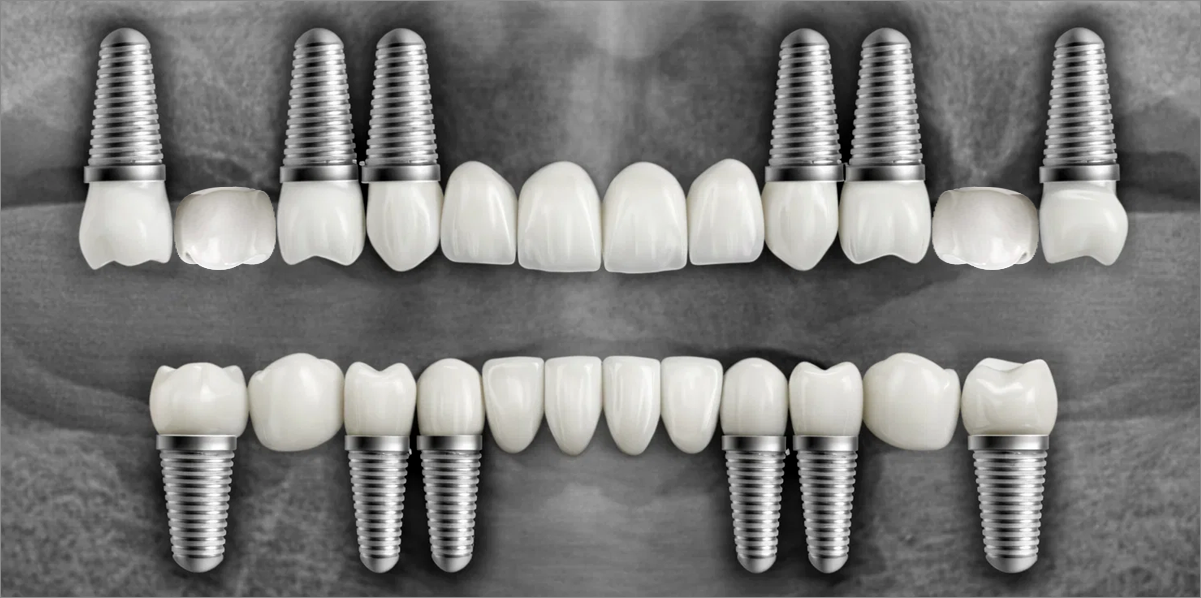

Full PlacementUsing a method of placing 8–9 implants in the maxilla and 8 implants in the mandible, this approach fully restores all 28 natural teeth, creating an oral environment most closely resembling

natural dentition. -

02

Minimal PlacementUsing a method of placing 6–7 implants in the maxilla and 6 in the mandible, this approach restores both posterior and anterior teeth, efficiently rehabilitating the entire oral cavity.